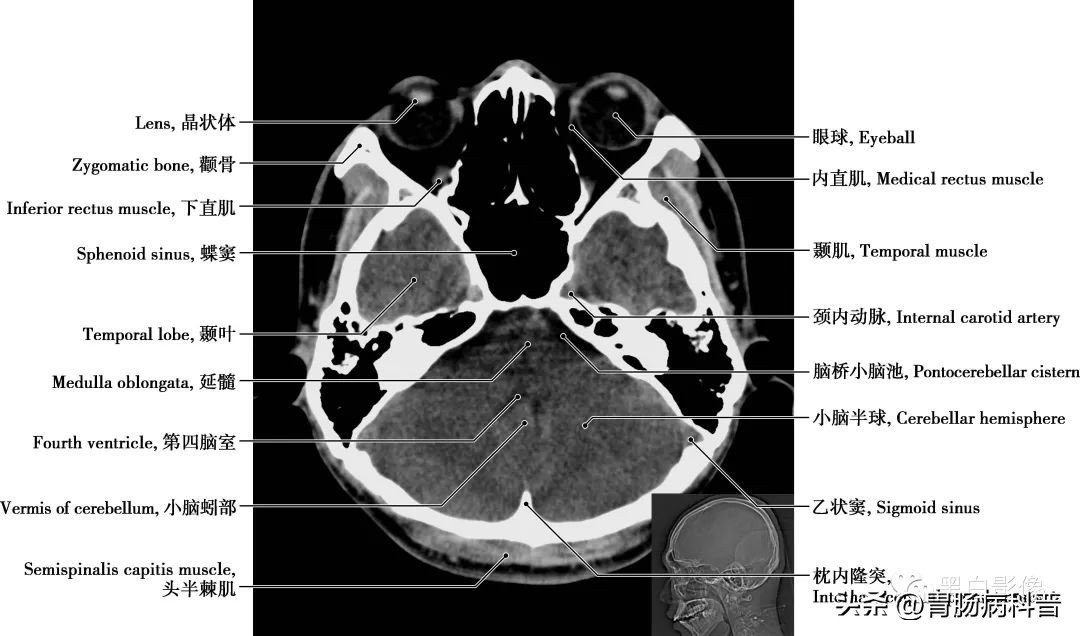

图1-1-15 经第四脑室下部轴位切面

乙状窦 是两侧横窦前下方的延续,横窦离开小脑幕边缘以柔和的“S”形曲线形成乙状窦流入颈静脉球,乙状窦最后变成双侧颈内静脉而终止。颈内动脉 分为颅外段和颅内段,颅内段分为C 1 颈段、C 2 岩段、C 3 破裂(孔)段、C 4 海绵窦段、C 5 床段、C 6 眼段和C 7 交通段。分支分布于视器和脑

图1-1-17 经第四脑室正中孔轴位切面

延髓 居于脑的最下部,与脊髓相连,上接脑桥,其主要功能为控制基本生命活动,如控制呼吸、心跳、消化等。延髓向下经枕骨大孔连接脊髓。乳突 位于鼓室的后下方,为外耳门后方的骨性突起,含有许多大小不等的气房,称乳突小房,各气房彼此相通,与鼓室之间的鼓窦相通